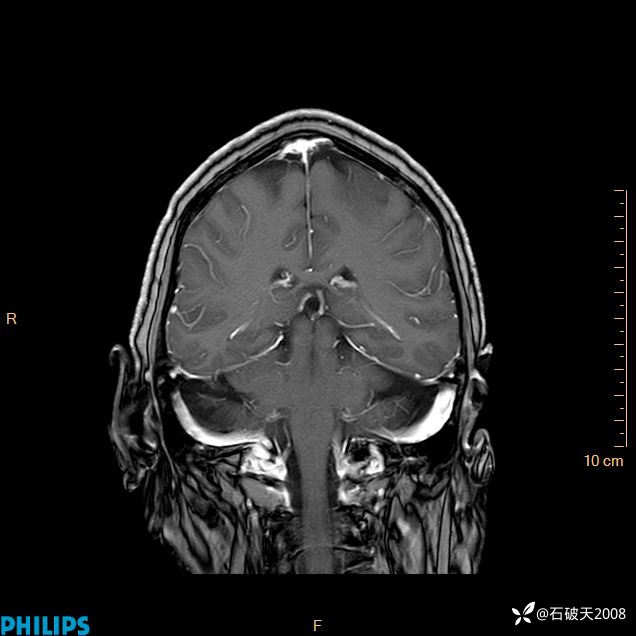

2024.2.21MR

增强冠状位